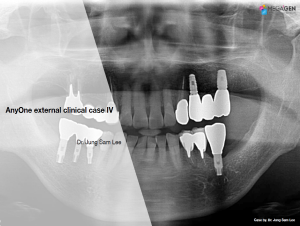

Dr. Achraf Souayah,Edentulous,Aesthetic zone,Maxillary Anterior,Maxillary Posterior,Mandibular Anterior,Mandibular Posterior,Guided surgery,Sinus Elevation,Immediate Placement,AnyRidge,Overdenture system,Meg-Rhein,MILA Kit,Clinical case